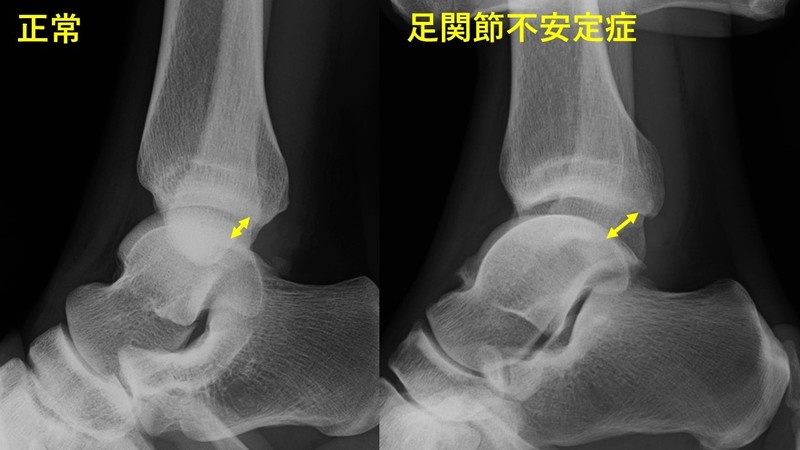

足関節ストレス撮影

例)

前方引き出し(Anterior drawer)

前後方向の緩さを確認する撮影方法です。

正常と比べると不安定症では緩さ(黄色矢印幅)が大きいのがわかります。

正常値:0~3mm